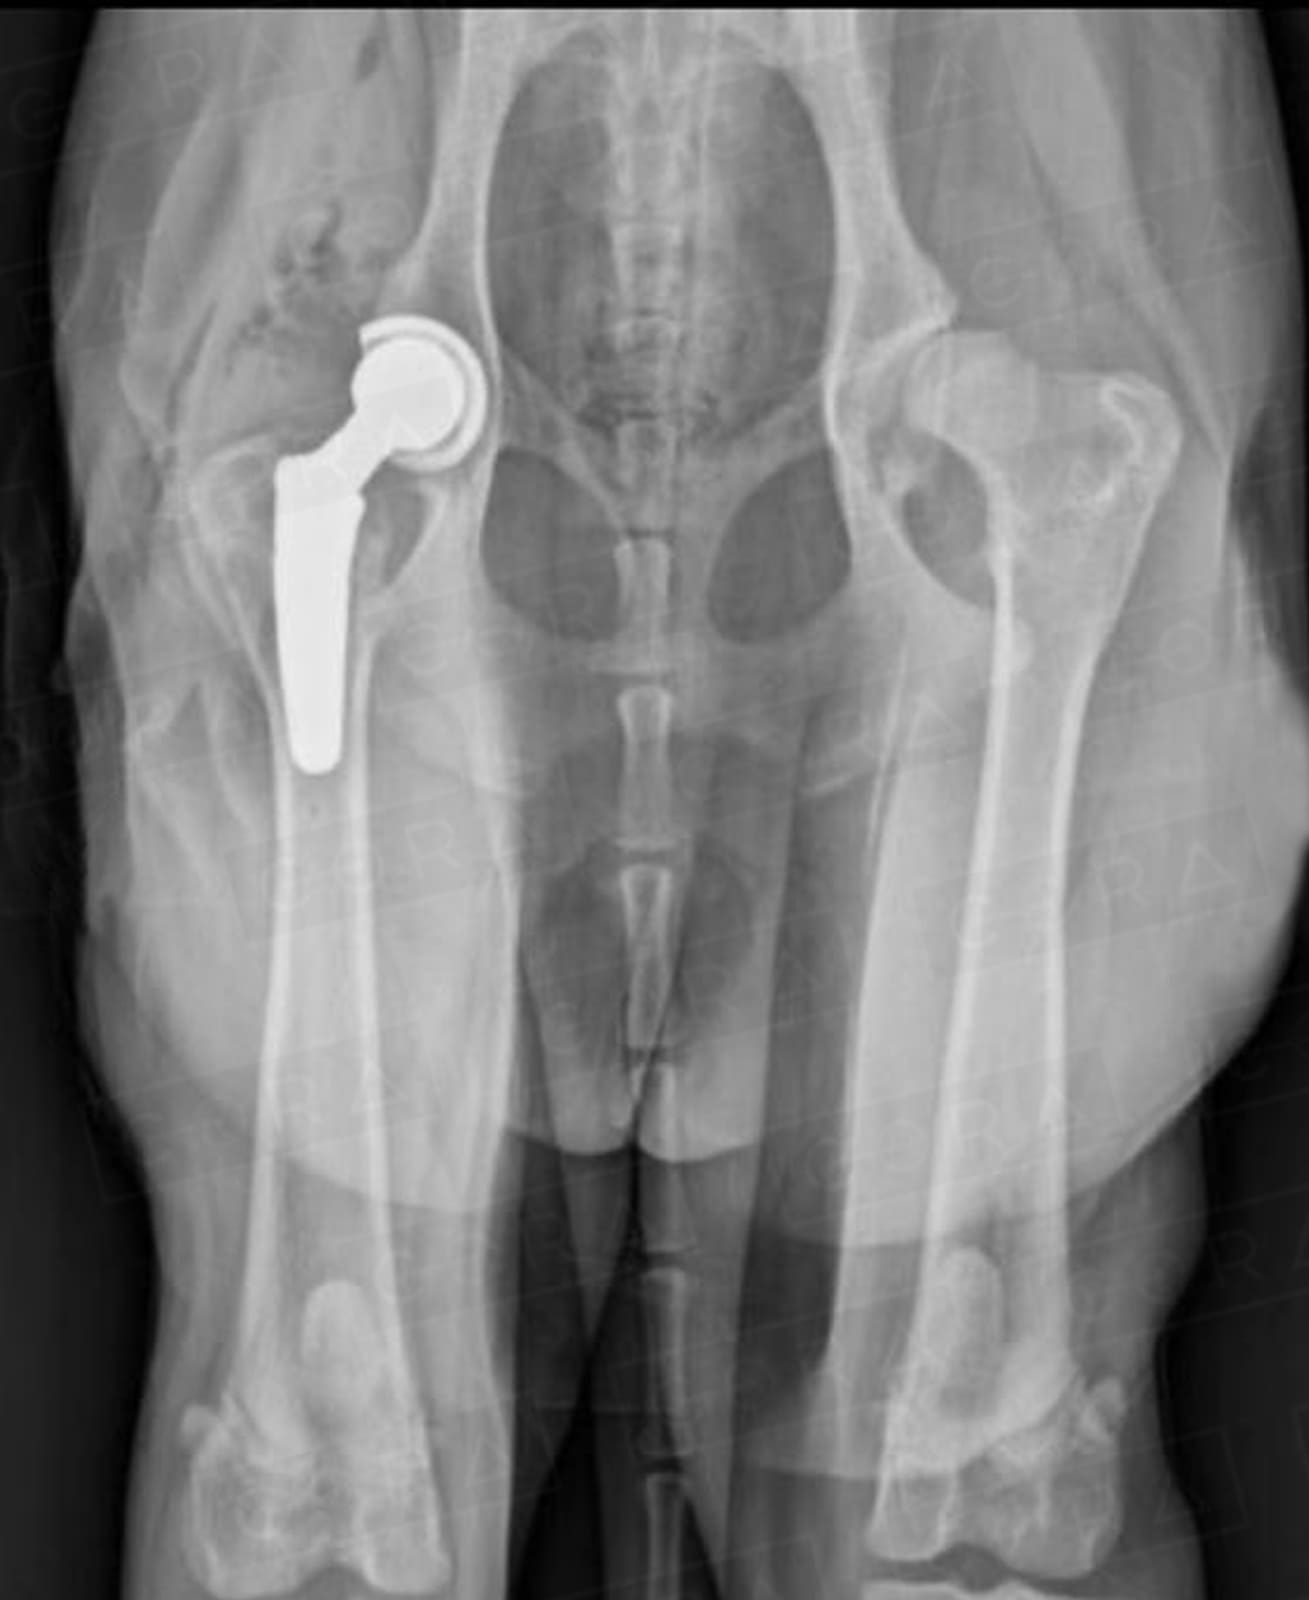

5. Prótese de quadril

Essa técnica, padrão ouro para a doença, visa a substituição completa da articulação por uma prótese, proporcionando o retorno completo da função do membro operado. (clique aqui para saber mais sobre prótese de quadril)